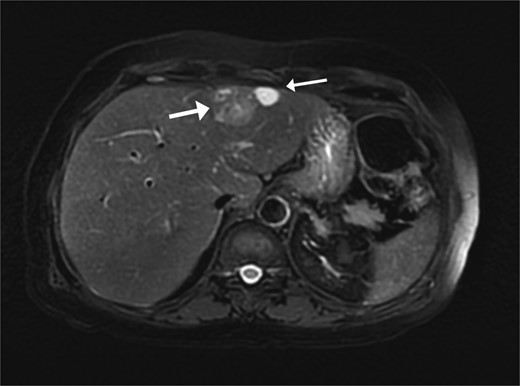

A 74-year-old man with right-handed colon cancer presented at the Emergency Department with a symptomatic anemia following chemotherapy and surgical intervention one year prior to the hepatocellular carcinoma resection. He reported 1-month history of paleness, dizziness, and exertional dyspnea, and fatiguability. Physical examination results were unremarkable. A chest CT angiography did not reveal a pulmonary embolism; however, two hepatic lesions, measuring 3.5 cm and 1.5 cm, in segment II were noted incidentally. Therefore, further laboratory tests were performed; hepatitis C virus was detected with a liver cirrhosis Child-Pugh score indicating class A disease; however, no tumor markers were detected. An abdominal CT revealed the two hepatic lesions in segment II, the larger lesion (3.8 cm × 3.4 cm) demonstrated arterial enhancement and faint washout in the delayed phase (Fig. 1). The smaller lesion measured 1.2 cm × 1.1 cm (Fig. 1). An abdominal MRI was performed to characterize the hepatic lesions: one lesion was consistent with HCC and the second was metastatic from mucinous which was visible previously on imaging at the time of diagnosis of colon cancer (Fig. 2). Furthermore, the biopsy of the two liver lesions confirmed the diagnoses of HCC and metastatic colon cancer. Subsequently, the case was discussed within a multidisciplinary tumor board (MDTB), where the decision was made to perform chemotherapy and trans arterial chemoembolization for the HCC lesion. Upon follow-up evaluation, segment II hepatic lesion size had decreased to 1.6 × 2.4 cm (previously was 3.8 × 3.4 cm) and 1.5 × 1.3 cm (previously 1.2 × 1.1 cm). Consequently, the case was rediscussed in MDTB, and it was decided to proceed with liver resection of the two lesions. Following this, the patient underwent left lateral lobectomy, common hepatic artery dissection, porta hepatis lymph node dissection, and cholecystectomy. Postoperative pathology showed a residual 2.3-cm-sized differentiated HCC and a metastatic colonic-type adenocarcinoma with a mucinous differentiation which was 1.2 cm in size. The two lesions measured 0.7 cm apart (Fig. 3). All lymph nodes dissected from the porta hepatis, and the common hepatic artery were positive for metastatic colonic type adenocarcinoma. The patient’s postoperative course was unremarkable, and he was discharged 12 days later. Following a discussion within the MDTB, it was decided to continue adjuvant chemotherapy.

The liver lesions in segment II. The largest lesion is 3.3 × 3.4 cm and demonstrates arterial enhancement and faint washout in the delayed phase. In the portovenous phase, the smaller lesion is 1.2 × 1.1 cm.